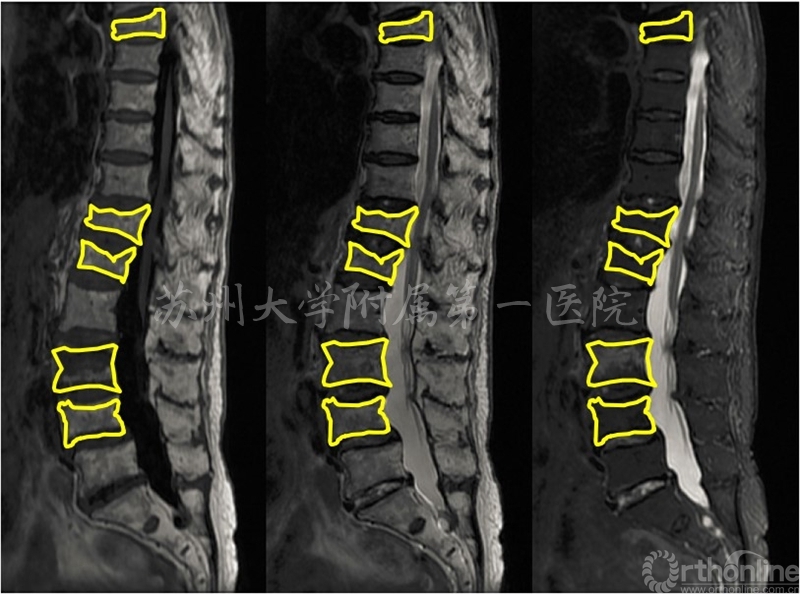

患者夏×,女性,97岁,胸7、胸12、腰1、腰3、腰4椎体骨折

患者夏×,女性,97岁,腰3为疼痛责任椎体,行KP治疗

97岁的夏阿婆,在剧烈咳嗽后出现腰背痛,去苏大附一院求诊,影像学检查竟然提示有胸7、胸12、腰1、腰3、腰4共5个椎体骨折!这么高的年龄和这么多骨折节段,还能手术治疗吗?

杨惠林教授团队仔细分析夏阿婆的症状、体征和影像学检查,通过创新技术,最后判定只有腰3是导致夏阿婆疼痛的罪魁祸首,即“疼痛责任椎体”。仅对腰3骨折行微创KP手术治疗后,夏阿婆腰背疼痛迅速缓解,术后1天即下地行走,3天出院。前不久,夏阿婆刚刚度过她的百岁寿辰。